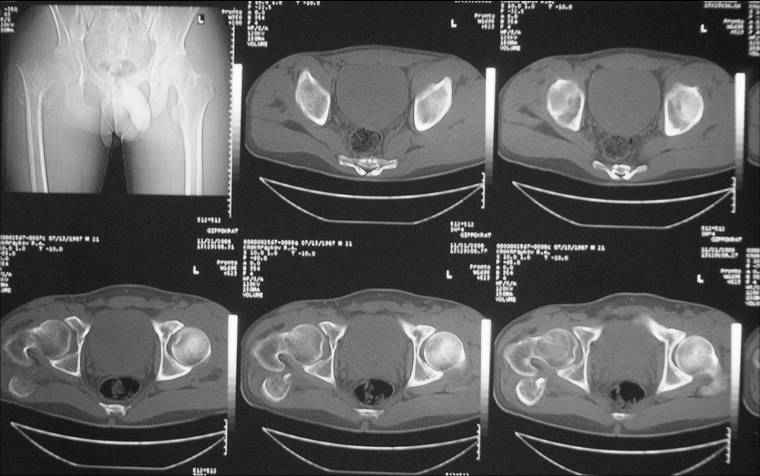

Уважаемые коллеги! Нужен совет. Больной Х., 21 год, ДЗ: ложный сустав вертельной области правого бедра.

Травма 8 мес. назад, ДТП, получил закрытый межвертельный перелом правого бедра. Лечился в городской больнице одного из городов-спутников г. Караганды скелетным вытяжением в течение 3 недель, затем кокситной гипсовой повязкой 2 мес. В настоящее время имеется укорочение конечности на 7 см, умеренная боль в вертельной области; ходит без костылей, полностью нагружая больную конечность, при нагрузке отмечается смещение дистального отломка проксимально примерно на 1,0 см.; объем движений в коленном суставе сохранен; при пальпации отломков боли нет, умеренная патологическая подвижность. Планируем внеочаговый остеосинтез спице-стержневым аппаратом, дистракция до восстановления длины бедра, вторым этапом остеосинтез стержнем Гамма. Есть надежда, что на дистракции пойдет сращение и у больного хватит терпения завершить лечение в аппарате.